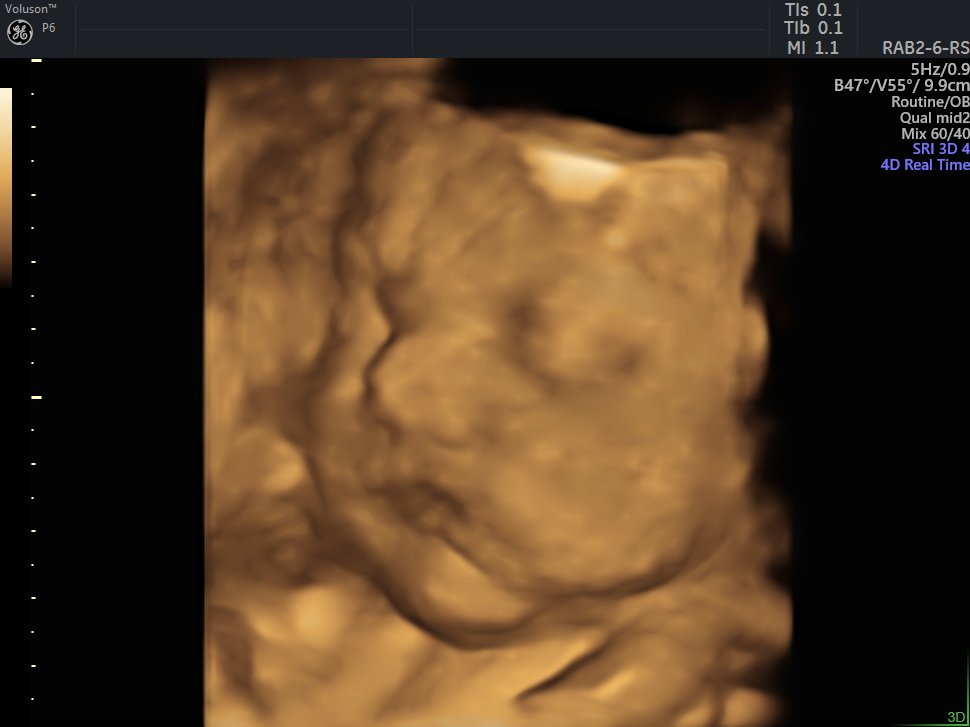

4 Boyutlu (Renkli) Ultrason ve Doppler Ultrasonografi

4 D Ultrasonografi